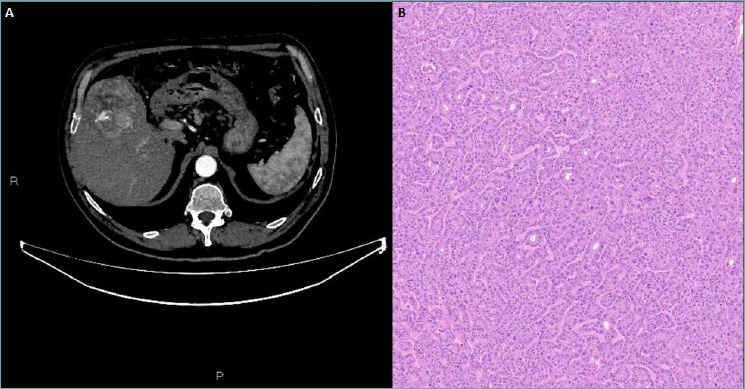

Hepatocellular carcinoma typically metastasizes within the liver and may involve extrahepatic sites such as the lungs, adrenal glands, and bones at advanced stages. However, hepatocellular carcinoma metastasis to the thyroid is very uncommon and tumor-to-tumor metastasis from a hepatocellular cancer to a thyroid neoplasm is extremely rare. In this report, we present a case of a 70-year-old man with a hepatocellular carcinoma metastasizing to oncocytic thyroid carcinoma, emphasizing the importance of clinical history and of a multidisciplinary approach, as well as the usefulness of site-specific immunohistochemical markers, in diagnosing and managing cases of Rosai's metastasis, especially when donor and recipient neoplasms share similar histologic features.

Abstract Image